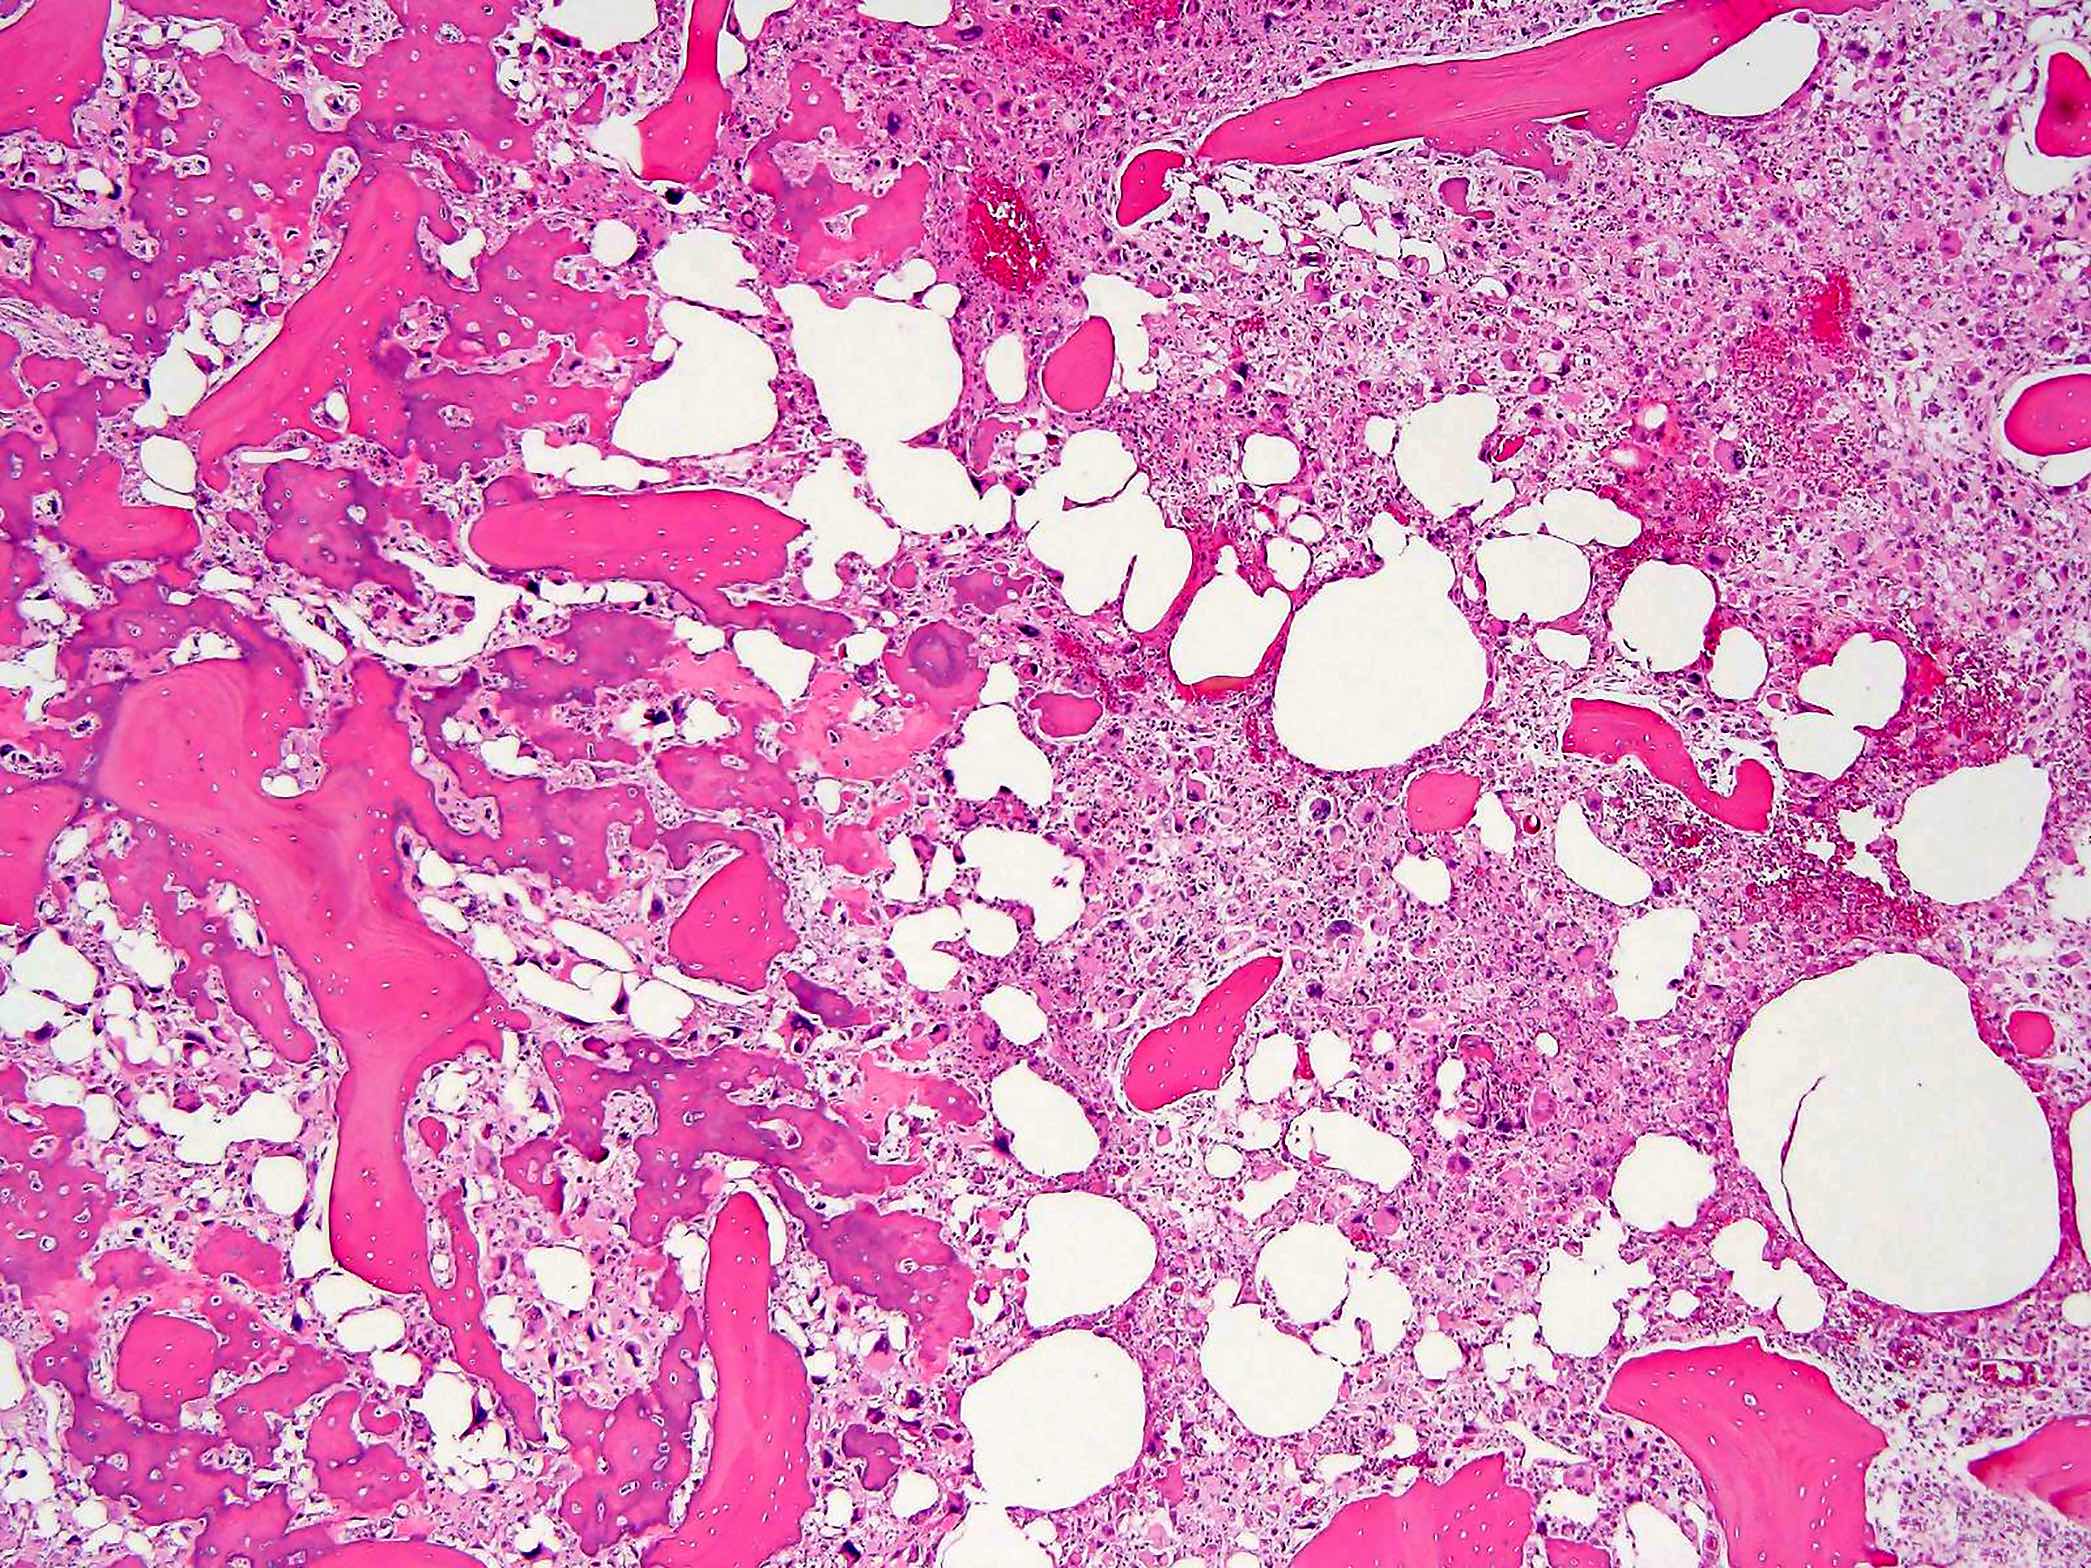

- Conventional (high grade intramedullary) osteosarcoma (Eur J Cancer 2002;38:1218, Am J Clin Pathol 2006;125:555):

- Permeative growth: intramedullary permeative growth (replacement of medullary space, surrounds and erodes native trabeculae, fills Haversian systems) and cortical destruction with soft tissue invasion

- Neoplastic cells: marked atypia (pleomorphic, hyperchromatic)

- Multiple cell morphologies often present in 1 tumor (epithelioid, plasmacytoid, spindled, small round cells, clear cells, giant tumor cells)

- Mitotic figures are easily demonstrable and atypical mitotic figures may also be identified

- Neoplastic bone (necessary for diagnosis): no minimum quantity necessary

- Most common: filigree / lace-like disorganized woven bone (intimately associated with neoplastic cells)

- Broad sheets of bone

- Normalization: decreased cytologic atypia of neoplastic cells entrapped in the bone matrix

- Scaffolding (appositional neoplastic osteoid deposition): deposition of neoplastic osteoid on native trabeculae

- Nonneoplastic giant cells: ~25% of cases

- Histologic subtypes of conventional osteosarcoma: no prognostic significance

- Osteoblastic, chondroblastic and fibroblastic are based on the prominent matrix they secrete (often admixed in 1 tumor)

- Osteoblastic osteosarcoma: the predominant matrix is neoplastic bone (as described above)

- Status postneoadjuvant chemotherapy:

- Report treatment response as a percent tumor necrosis (really an assessment of tumor drop out)

- Edematous scar: loose edematous to myxoid granulation tissue, fibrosis, mild chronic inflammation

- Bony matrix remains

- Residual tumor cells: nests of tumor cells in retraction clefts are common